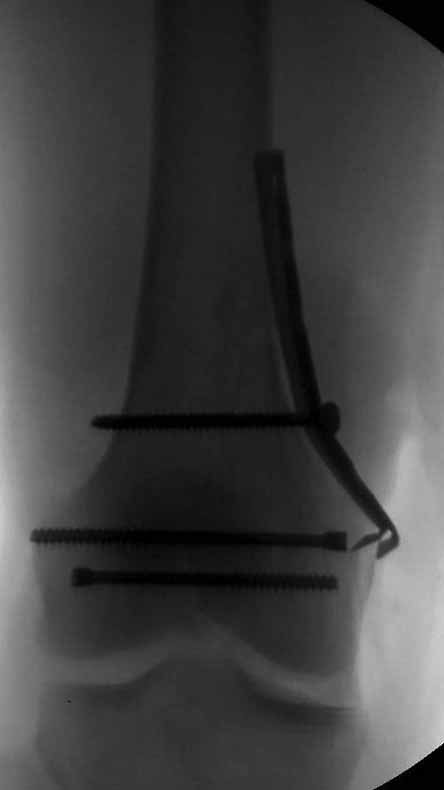

И уже лет шесть мы используем возможность ввести в дистальное овальное отверстие 3 винта, которые именно запираются в этом отверстии, не люфтят, а обеспечивают угловую стабильность - см картинку.

Получается и стабильно, и очень дистально, нижний край отверстия в 3 мм от дистального конца гвоздя.

В приложении пример недавней операции, C3, открытая репозиция, фиксация мыщелков спицами и винтами, ретроградный синтез большеберцовым гвоздем 10,5 мм диаметром, винты 5 мм.